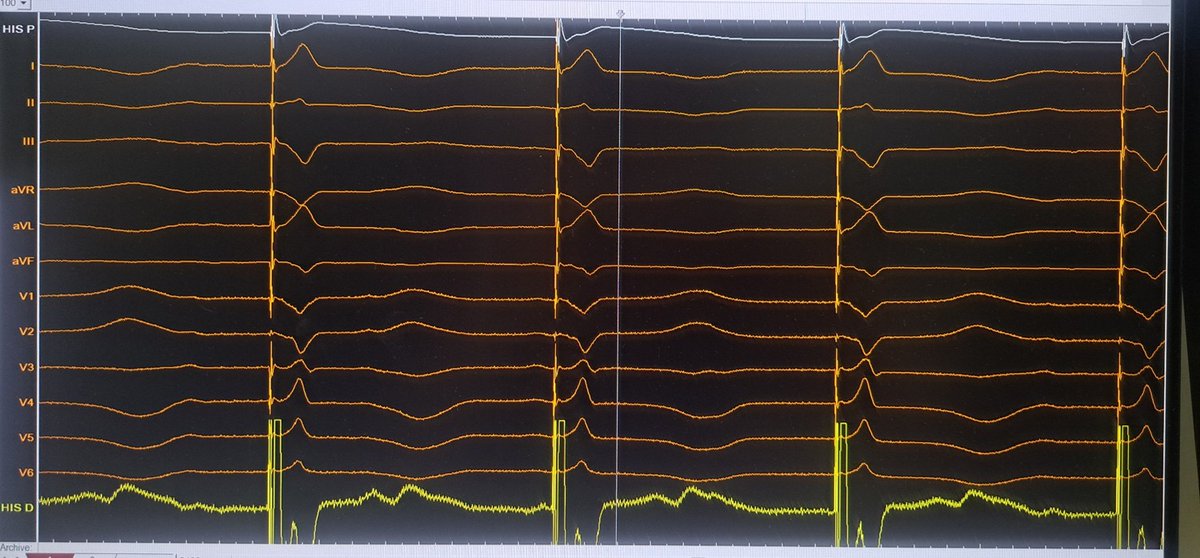

Challenging LOT CRT case. Final UHF ECG recordings very satisfactory @curilakarol @MirekNavratil1 #Epeeps